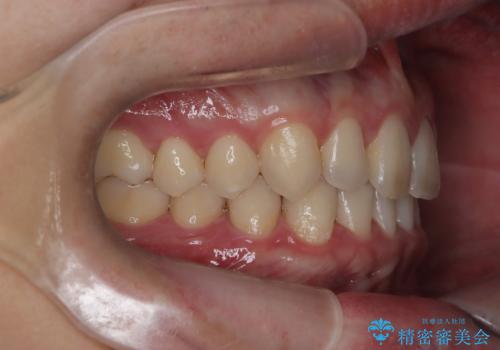

【インビザライン】前歯の隙間を治したい。

- 前歯の隙間を主訴に来院されました。

インビザラインにて治療しました。

ディープバイトも改善でき患者さんも満足されていました。

前歯の隙間だけを閉じる治療を行うだけでは、噛み合わせが悪くなるためディープバイトも改善が必要です。